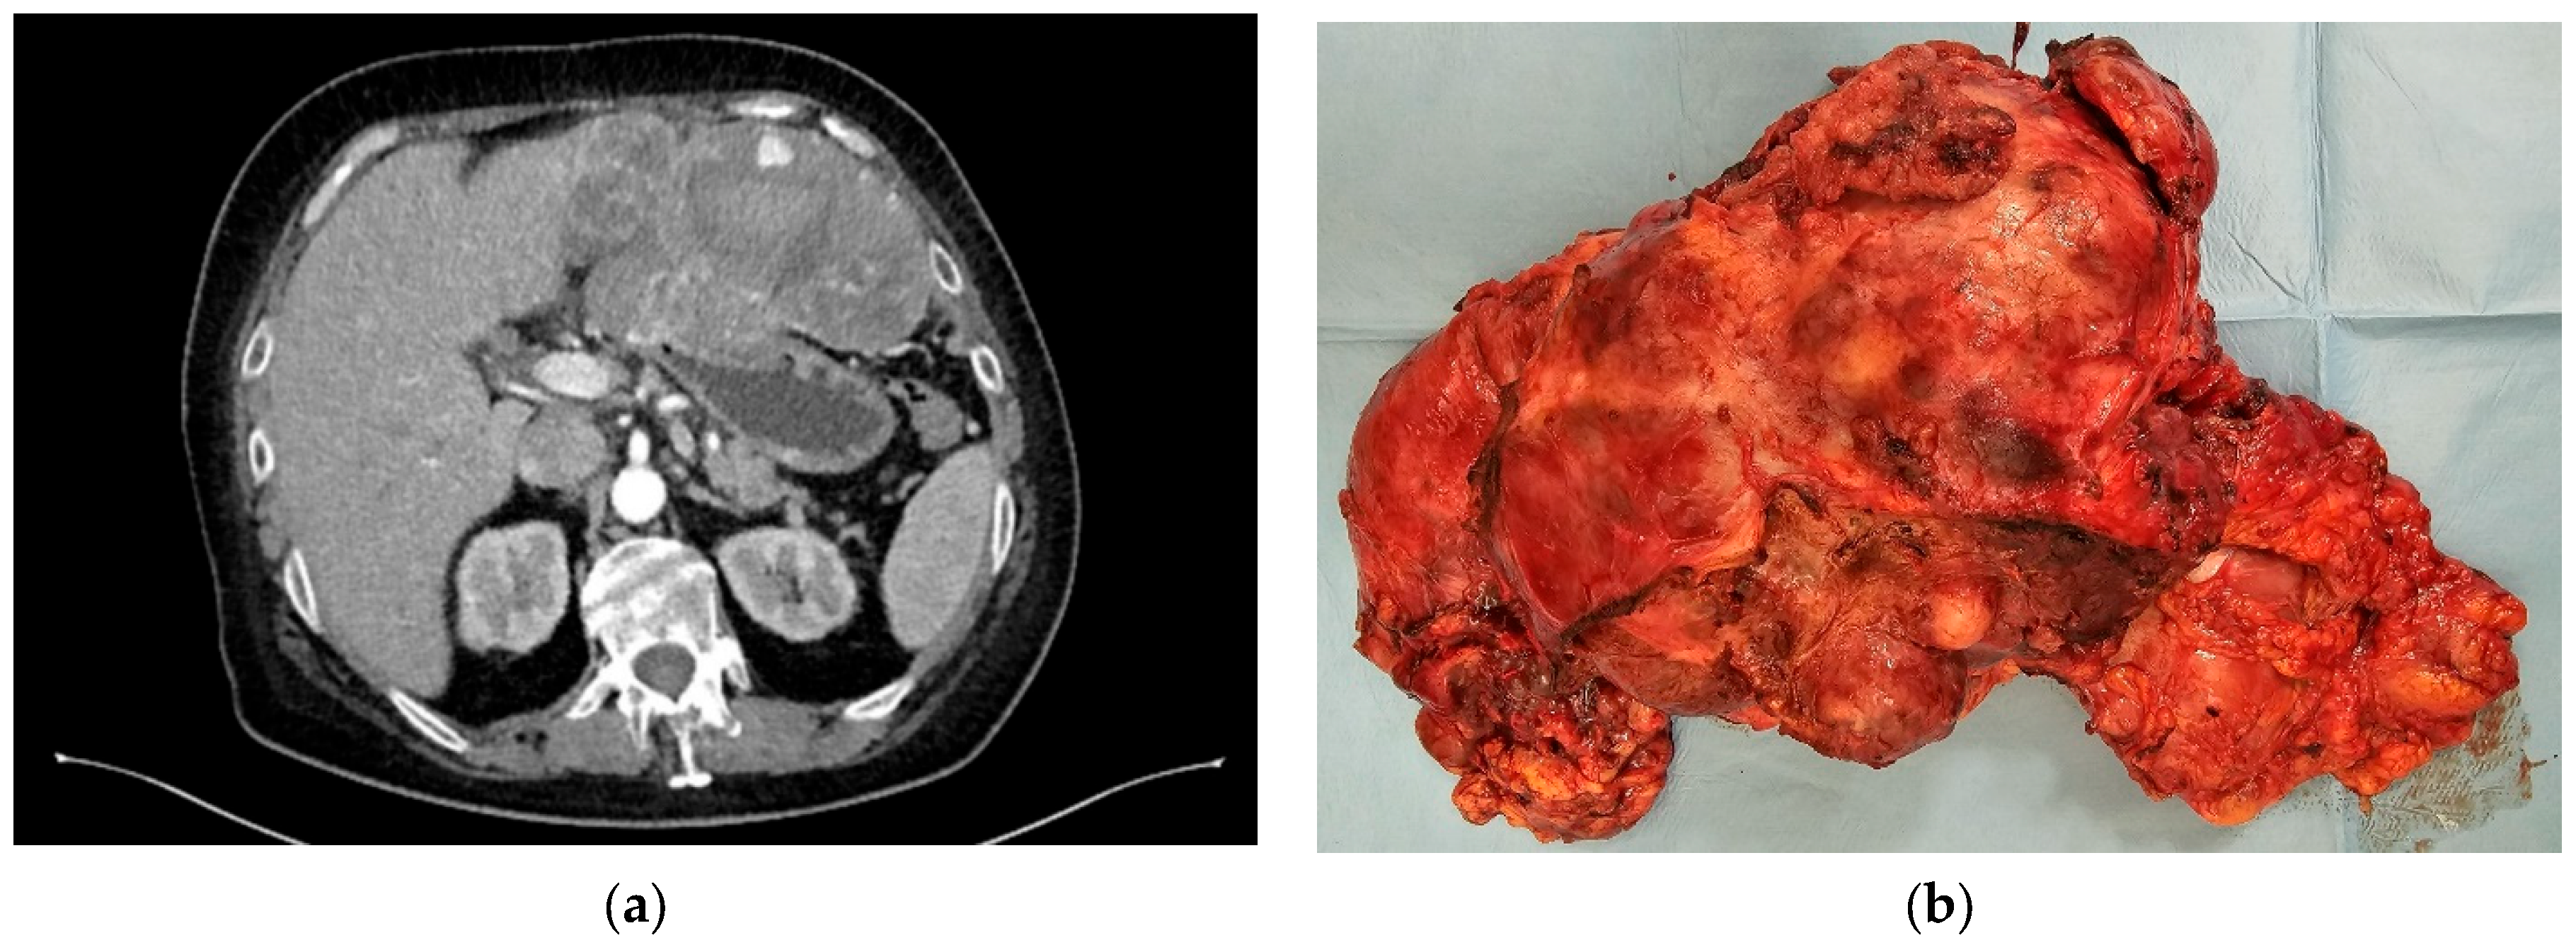

- Moga, D.; Popentiu, A.; Popa, D. Laparoscopic Wedge Resection for Gastric Mesenchymal Tumor–Small Case Series. Rom. J. Mil. Med. 2023, 126, 239–244. [Google Scholar] [CrossRef]

- Costache, M.F.; Filip, B.; Scripcariu, D.V.; Danilă, N.; Scripcariu, V. Management of Gastric Stromal Tumour-Multicenter Observational Study. Chirurgia 2018, 113, 780–788. [Google Scholar] [CrossRef] [PubMed]